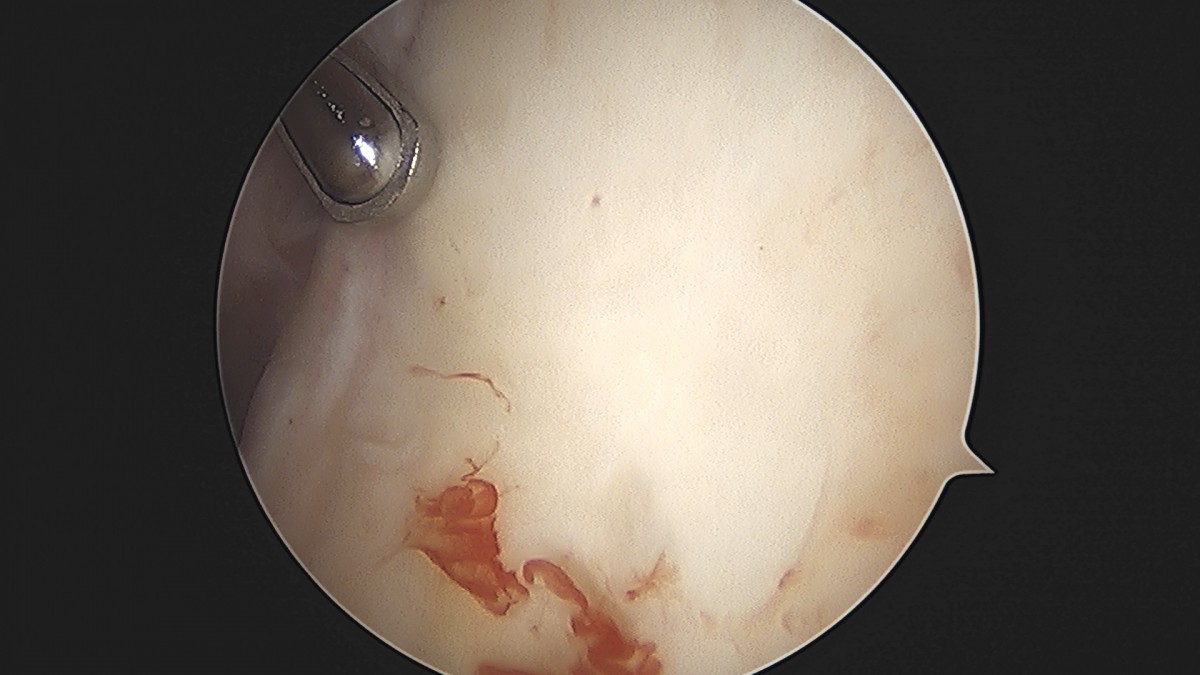

정지영원장님 어깨 관절낭 이완술 이상O 환자

작성자 최고관리자 댓글 0건 조회 743회 작성일 25-09-16 16:58